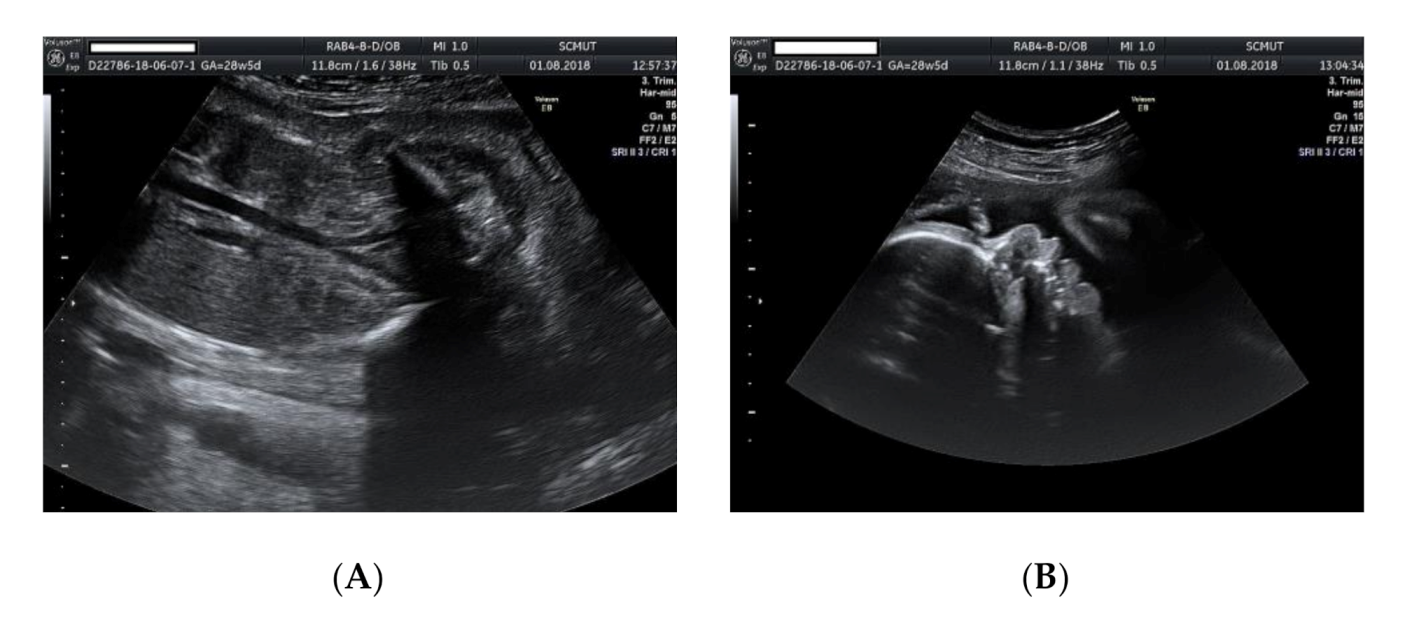

2. Case Presentation